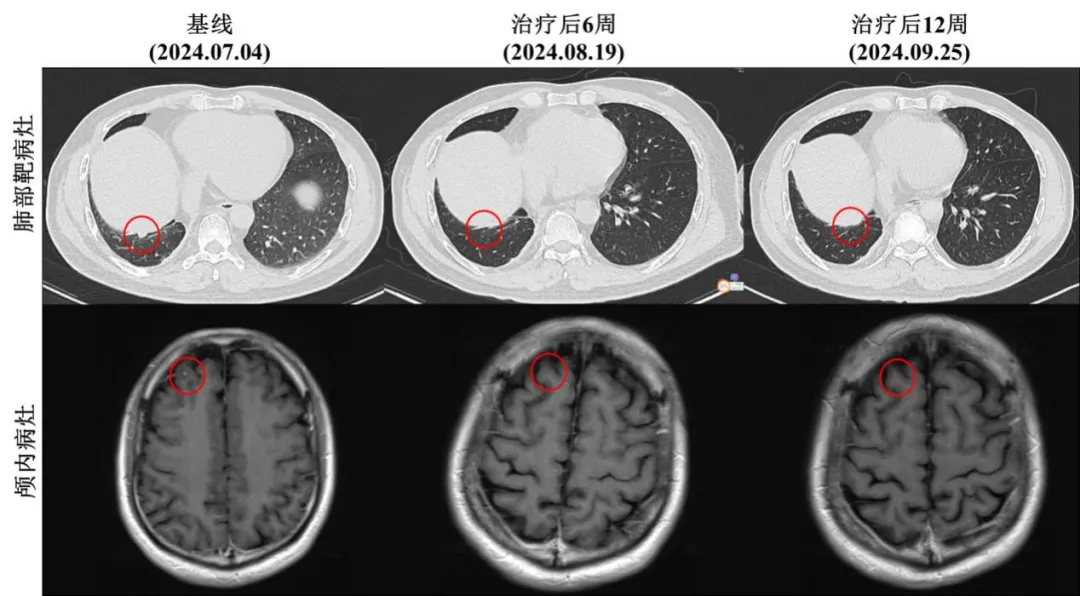

该患者符合Ficonalkib III期临床试验的入组标准,接受每日一次600 mg剂量的Ficonalkib胶囊口服治疗,每3周为一个给药周期。治疗6周后,增强CT和脑部MRI结果显示患者右肺下叶靶病灶完全消失,颅内非靶病灶完全消失(图1)。但肺部多发小结节、右侧胸膜结节及胸腔积液仍存在。根据实体瘤疗效评价标准(RECIST v1.1),患者达到部分缓解(PR)。

患者继续接受治疗,12周后的影像学检查显示,所有靶病灶和非靶病灶(包括肺部及头颅病灶)均完全消失(图1),患者达到完全缓解(CR)。表明Ficonalkib对该患者的肿瘤具有显著的抑制作用。

图1 | 患者在Ficonalkib治疗期间各病灶不同时间点的影像学检查结果